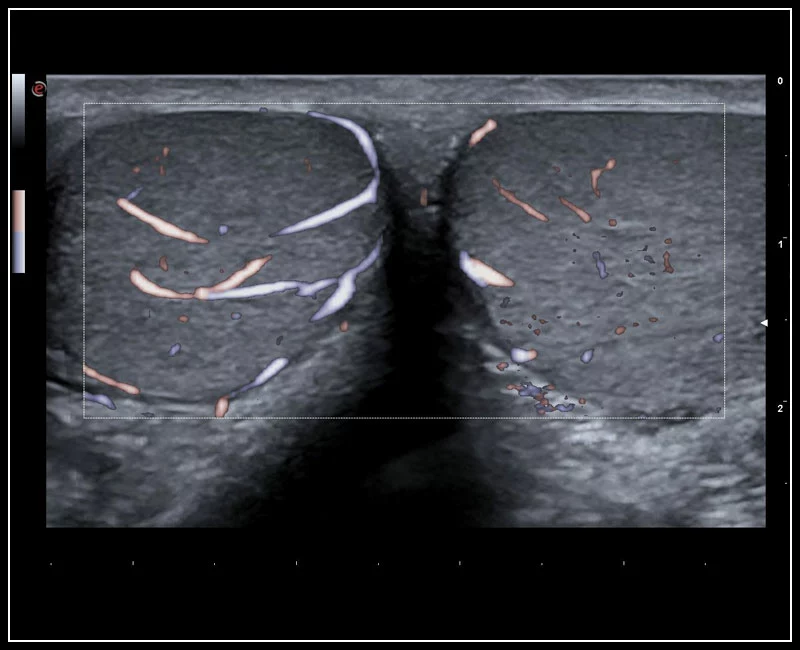

MyLab™9 Platform - High resolution imaging in testis

MyLab™9 Platform - High resolution imaging in testis

MyLab™9 Platform - XFlow in testis vascularization

MyLab™9 Platform - XFlow in testis vascularization

MyLab™C30 - Interventional B-Mode - Testis

MyLab™C30 - Interventional B-Mode - Testis